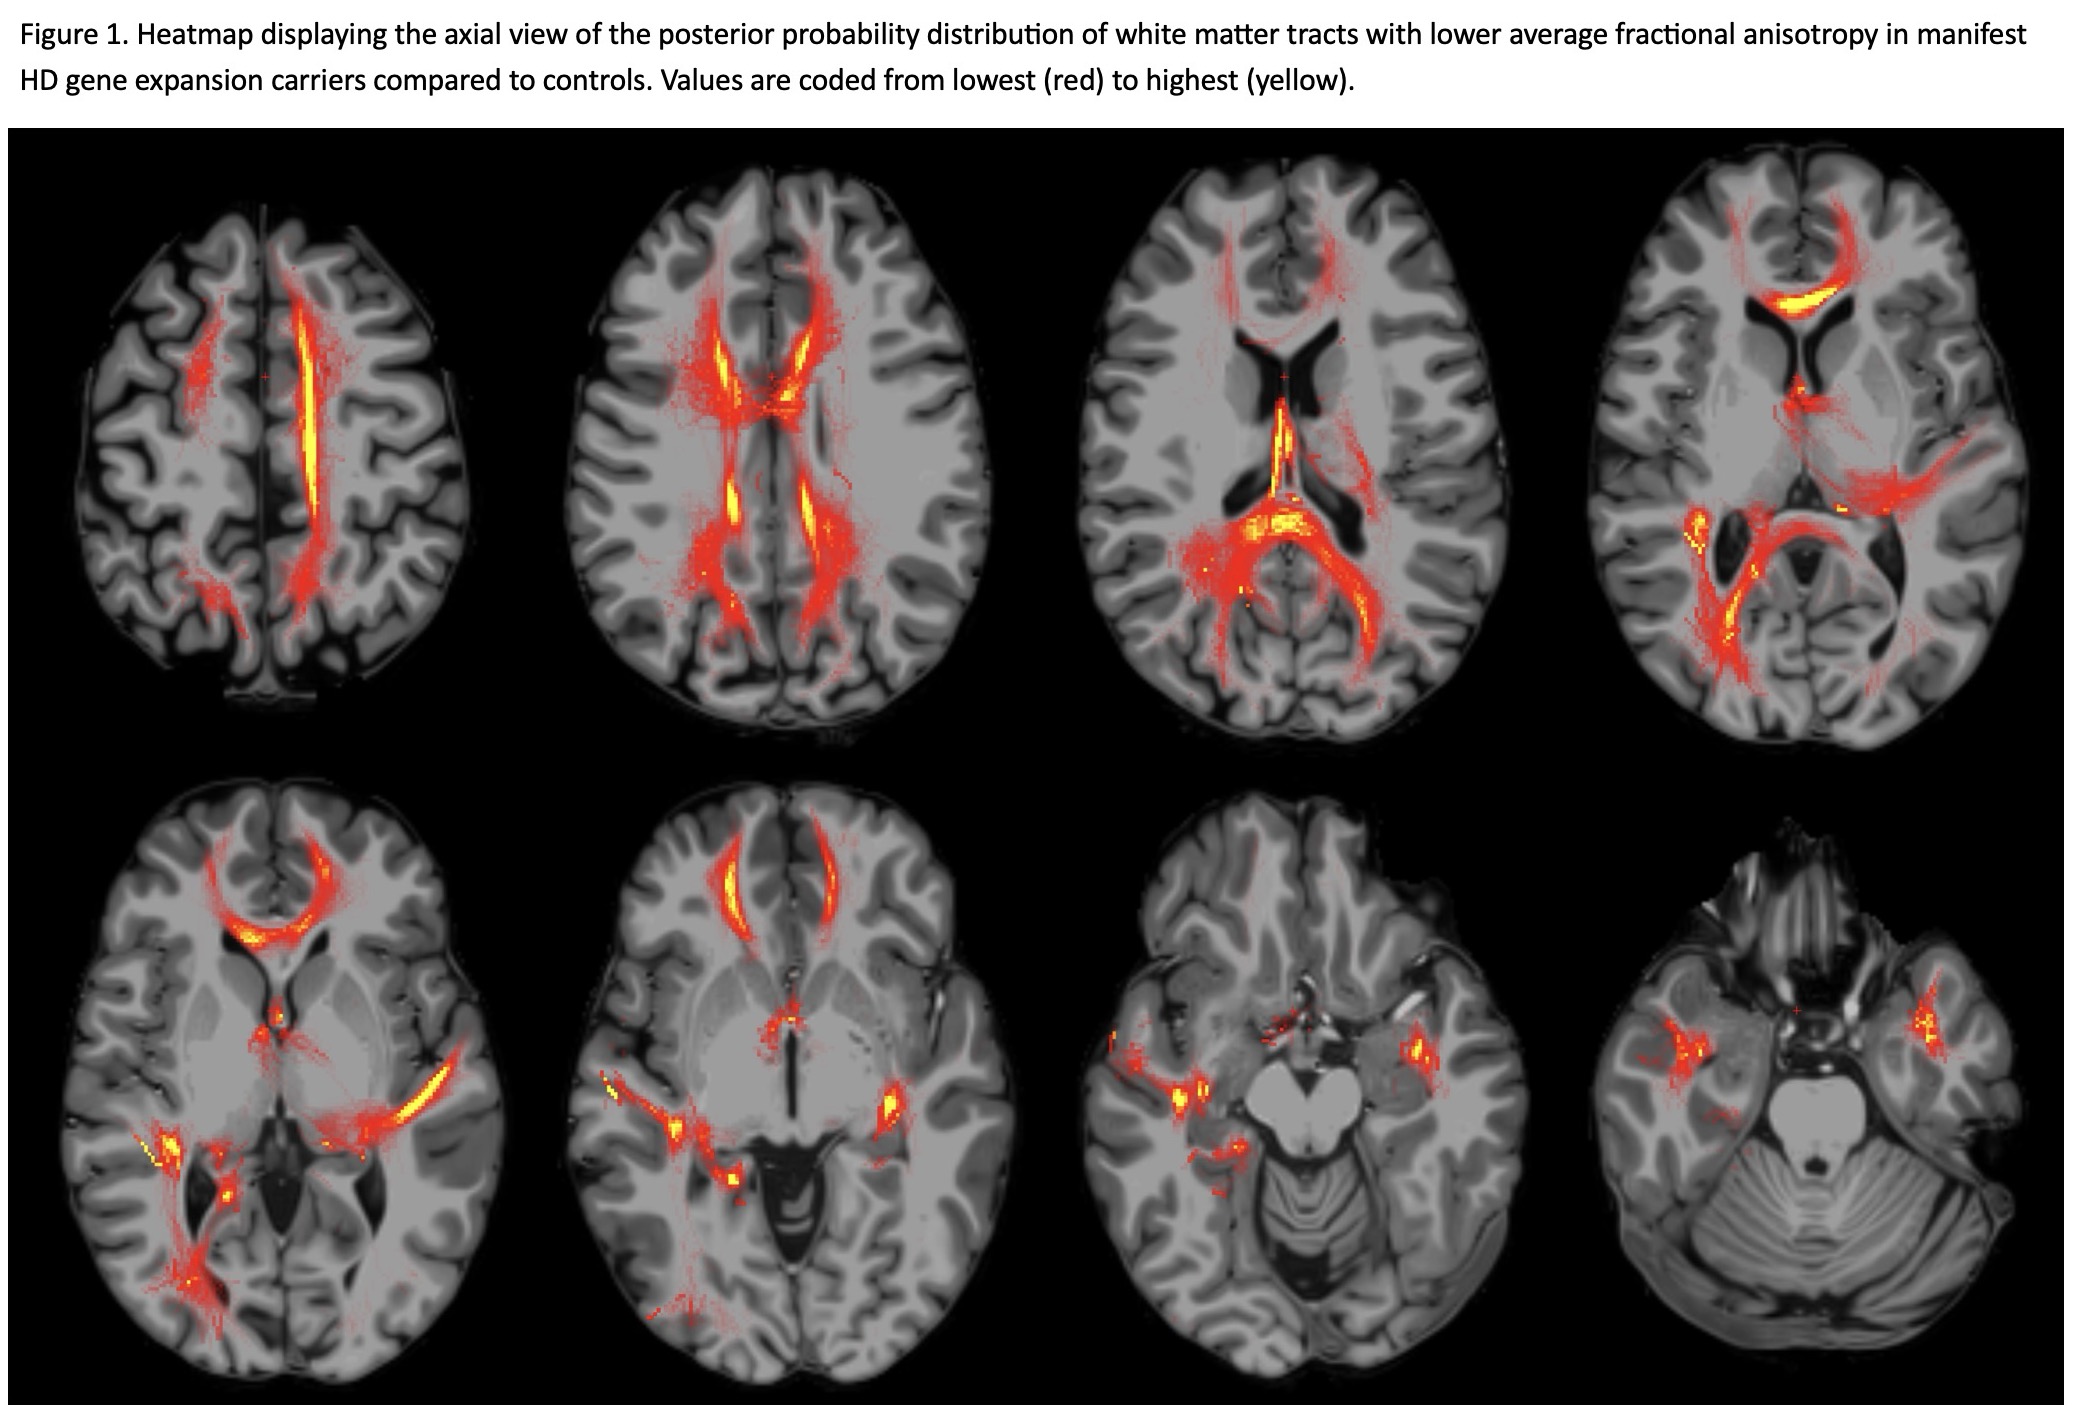

Results: Manifest HD patients exhibited significant and widespread white matter degeneration. MD was significantly increased in manifest HD compared to both premanifest HD and control groups across all pathways, except for the middle cerebellar peduncle [Table 1]. A corresponding decrease in FA was observed in many pathways in manifest HD compared to the other groups [Table 1, Figure 1]. No significant differences were found between the premanifest HD and controls. Additionally, greater white matter deterioration was significantly correlated with poorer performance on motor, functional capacity, and cognitive scales [Table 2].

Figure 1